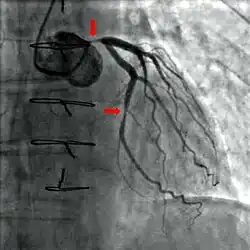

Jest to badanie mające na celu uzyskanie angiografu tętnic wieńcowych. Rodzaje koronarografii:

- Przezskórna koronarografia – w badaniu tym, środek kontrastowy dostarczany był do badanego miejsca z wykorzystaniem dostępu poprzez tętnicę udową. Obecnie jednak stosuje się dostęp poprzez tętnicę promieniową ze względu na spadek powikłań miejscowych czy skrócony czas hospitalizacji. Metoda ta ma jednak swoje wady – jest ona trudniejsza do opanowania oraz wymaga więcej cierpliwości, jednakże w ostatecznym rozrachunku korzyści ekonomiczne jak i również poprawienie samopoczucia pacjentów którzy mogą wcześniej opuścić szpital powoduje, iż jest to obecnie najczęściej stosowana metoda w badaniach koronarografii[6].